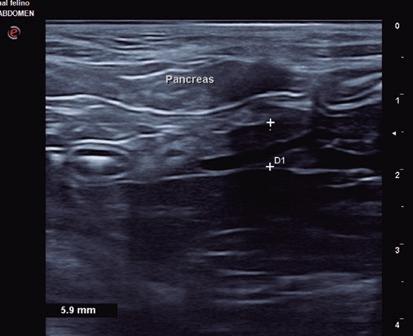

La ecografía es parte importante de los procedimientos de diagnóstico al servir para explorar la mayoría de los órganos del cuerpo. Las ondas ultrasónicas se emplean sobre todo para realizar la ecografía abdominal y la ecocardiografía. En la ecografía abdominal se explora la región abdominal junto con las venas y los ganglios linfáticos, y permite valorar alteraciones del hígado, los riñones, páncreas, y el útero, entre otros órganos. En la ecocardiografía se exploran el corazón, el pericardio y los vasos sanguíneos que llegan al corazón o salen de él.